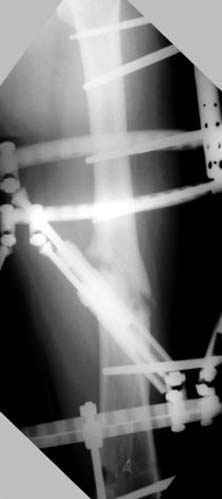

7:30 начало операции, больной на спине, попытка репозиции после анестезии N3, укладка больного на боку, доступ Kocher- Langenbeck, состояние седалищнего нерва около 2.5см кровоподтек, через joistick головка бедра приподнята, освобовождение сустава, фрагмент заднего края более 3х4 см репонирован на свое место. После промывания

сустава, репозиция вывиха (N4), фиксация фрагмента 2.7(4) мм шурупами и допольнительно реконструктивной пластиной на 8 дырок, фиксация 3.5мм шурупами проксимально и дистально.

Интраоперционные N5 косая запирательная и N6 подвздошный снимок